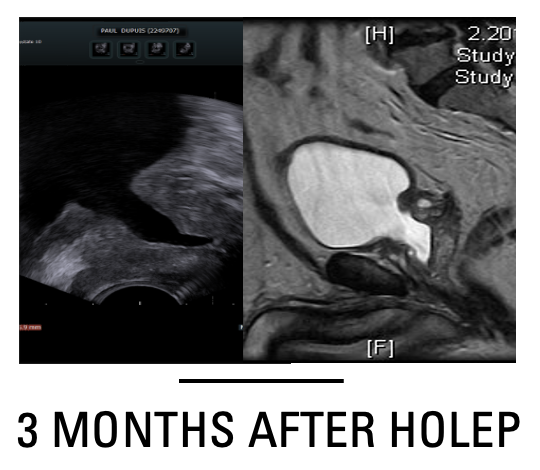

Veil sparing Holmium Laser Enculeation of the Prostate (Lobe by Lobe HoLEP)

Veil sparing HOLEP was performed in step manner approach abbreviated for sake of learning as (IT PAS ABCD). I, incision of the prostate from the deepest groove at the bladder neck till just lateral to the Veru Montanum. T, trough creation, it means widening the incision by incising underneath the 2 lateral lobes with slight pressure applied by the scope to have a wide channel allowing free flow of irrigant while doing apical dissection. This trough is similarly created if we have 2 deep grooves with prominent median lobe by enucleating median lobe first. P, plane development, this step is done by extending mucosal only incision laterally over the apical lateral bulge followed by blunt enucleation of the lateral lobe. A, apico-lateral dissection, it entails upward enucleation of the prostate apex till 3 O’clock position on the left and 9 O’clock position on the right. S, sphincter liberation or strip cutting, where the scope is rotated 180 degrees up with fiber facing 12 O’clock position and mucosal attachment of the adenoma is cut 1cm proximal to the veru (the adenoma should be stretched slightly towards the bladder neck) from 12 to 3 O’clock position on the left and from 12 to 9 O’clock position on the left. A, anterior dissection, where the adenoma is sharply dissected by cutting in arc-shape from the anterior commissure towards the previously developed apico-lateral plain. Anterior dissection in the distal one third of the prostate entails sharp cutting leaving a veil of tissue anteriorly where a capsular plain is poorly identifiable. Later a combined sharp and blunt dissection could easily develop a capsular plain that continues laterally. B, bladder neck dissection, once the bladder neck fibers are identified anteriorly, they were cut transversely by laser. C, c-shaped baso-lateral dissection, at this stage the scope is rotated in c-shaped manner from 12 to 4 O’clock positions on the left and from 12 to 8 O’clock positions on the right. In this step sharp laser dissection is used while applying pressure on the adenoma pushing it from lateral to medial. The rotating movements were repeated while withdrawing the scope inside the prostate fossa till joining the previously formed apico-lateral and basal capsular plains. D, detachment and flipping of the adenoma, the adenoma is lifted by the scope toward the bladder neck till we can flip it to the bladder with remaining basal bladder neck attachment cut by laser from lateral to medial till being completely detached to the bladder. #HOLEP #ANATOMICAL ENDOSCOPIC ENUCLEATION OF THE PROSTATE #enucleation #prostate #learning visit our website https://mansoura-endoacademy.com/ Review the original article https://www.minervamedica.it/en/journals/minerva-urology-nephrology/article.php?cod=R19Y2024N02A0210